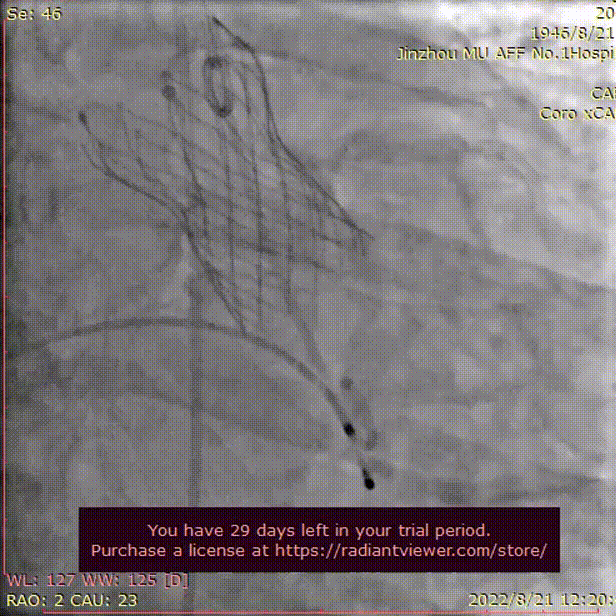

术中影像

LCA术前

LCA术后

RCA术前

RCA术后

主动脉根部造影

导丝跨瓣

TaurusElite AV26 瓣膜逐渐释放至工作位

工作位造影 瓣膜位置良好

冠脉灌注良好

瓣膜脱钩

最终位造影

形态良好 位置理想

微量瓣周漏 即刻跨瓣压差为5mmHg